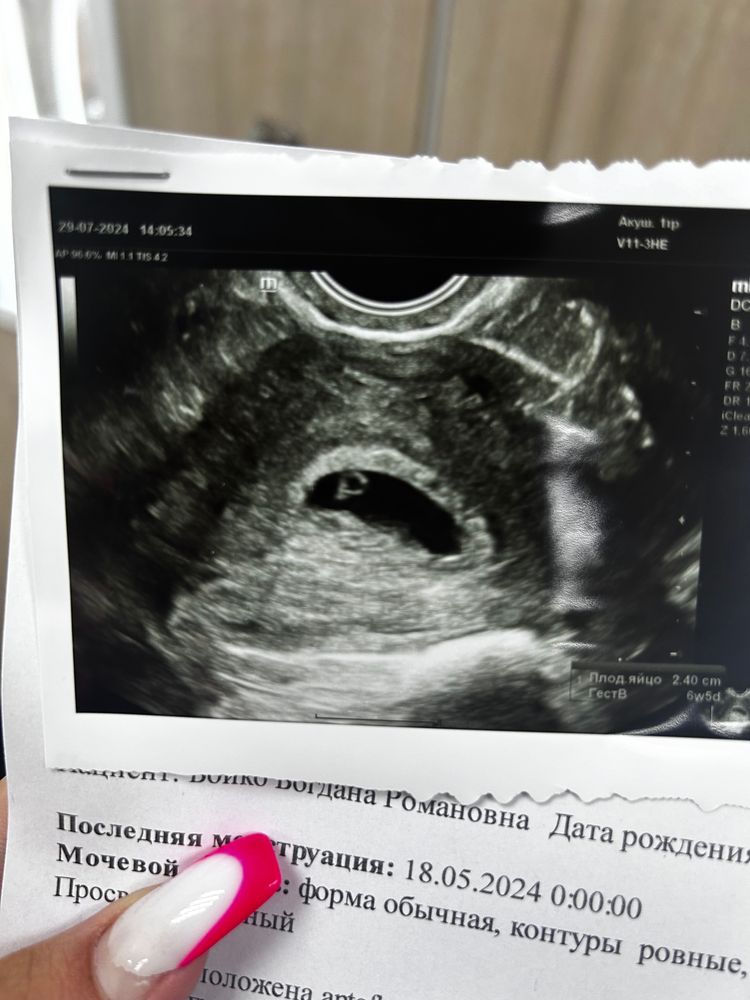

Так видно же эмбрион на фото, точка 1-2мм рядом с жм

Yana, она сказала просто структура это

Дарья Романовна, ну есть такие врачи, которые бзнуть лишнего боятся, поэтому все что чуть хуже видно называют - структура, включение Пя на ранних сроках у них включение А эмбрион у жм структура А какая структура она не сказала, потому что сама не знает, какая ещё может быть структура рядом с жм)

Дарья Романовна, кстати если присмотреться, то видно рядом с жм точечку, возможно это как раз эмбрион) все будет хорошо, главное не переживайте 🙏🏻

Ксения, вот она и сказала , что есть какая то структура похожая на эмбрион

Юля , плодное яйцо 2,40см , желточный мешочек тоже есть

Ровно 4 недели от зачатия или 6 акушерских недель) картина в принципе такая же) колечко с бриллиантом) плодное яйцо 24х8мм, желточный мешочек 3мм, сам эмбриончик 1мм. Сказали, что всё хорошо, только тонус есть. Вот эта белая точка у колечка и есть эмбриончик) так что я думаю, что переживать не стоит и нужно чуть позже переделать узи Изображение